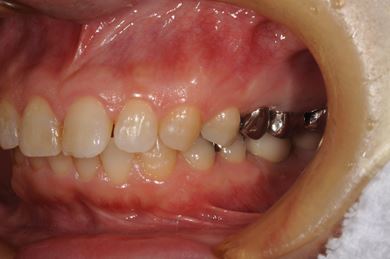

抜歯即日スピードインプラント治療+セラミック治療+歯肉歯槽骨整形術

| 性別/年齢 | 女性 / 39歳 | ||||||||||||||||||||||||||||||||

| 主訴 | 銀歯が取れたのでみて欲しい。 | ||||||||||||||||||||||||||||||||

| 治療方針 | 左下欠損部と保存不能の歯を抜歯し、インプラント治療にて機能的・審美的回復を行う。 | ||||||||||||||||||||||||||||||||

| 治療内容 | インプラント2本(抜歯即日スピードインプラント)、ハイブリッドセラミッククラウン2本、歯肉歯槽骨整形術 | ||||||||||||||||||||||||||||||||

| 総治療費 | 488,250円 | ||||||||||||||||||||||||||||||||

| 治療期間 | 1年4ヶ月 |